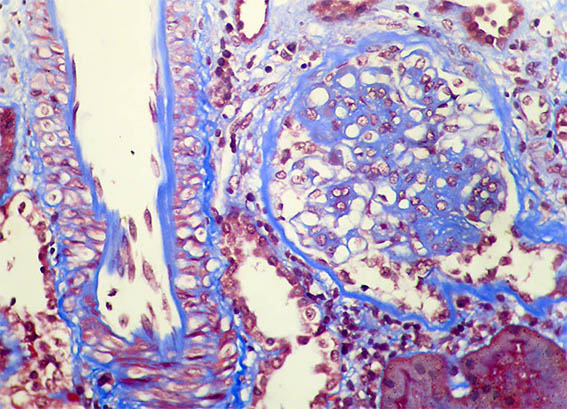

Figura 7. Tricrómico de Masson, X400. Un glomérulo con incremento de la matriz mesangial y una arteria normal.

Figura 8. Tricrómico de Masson, X400. Hipercelularidad endocapilar.